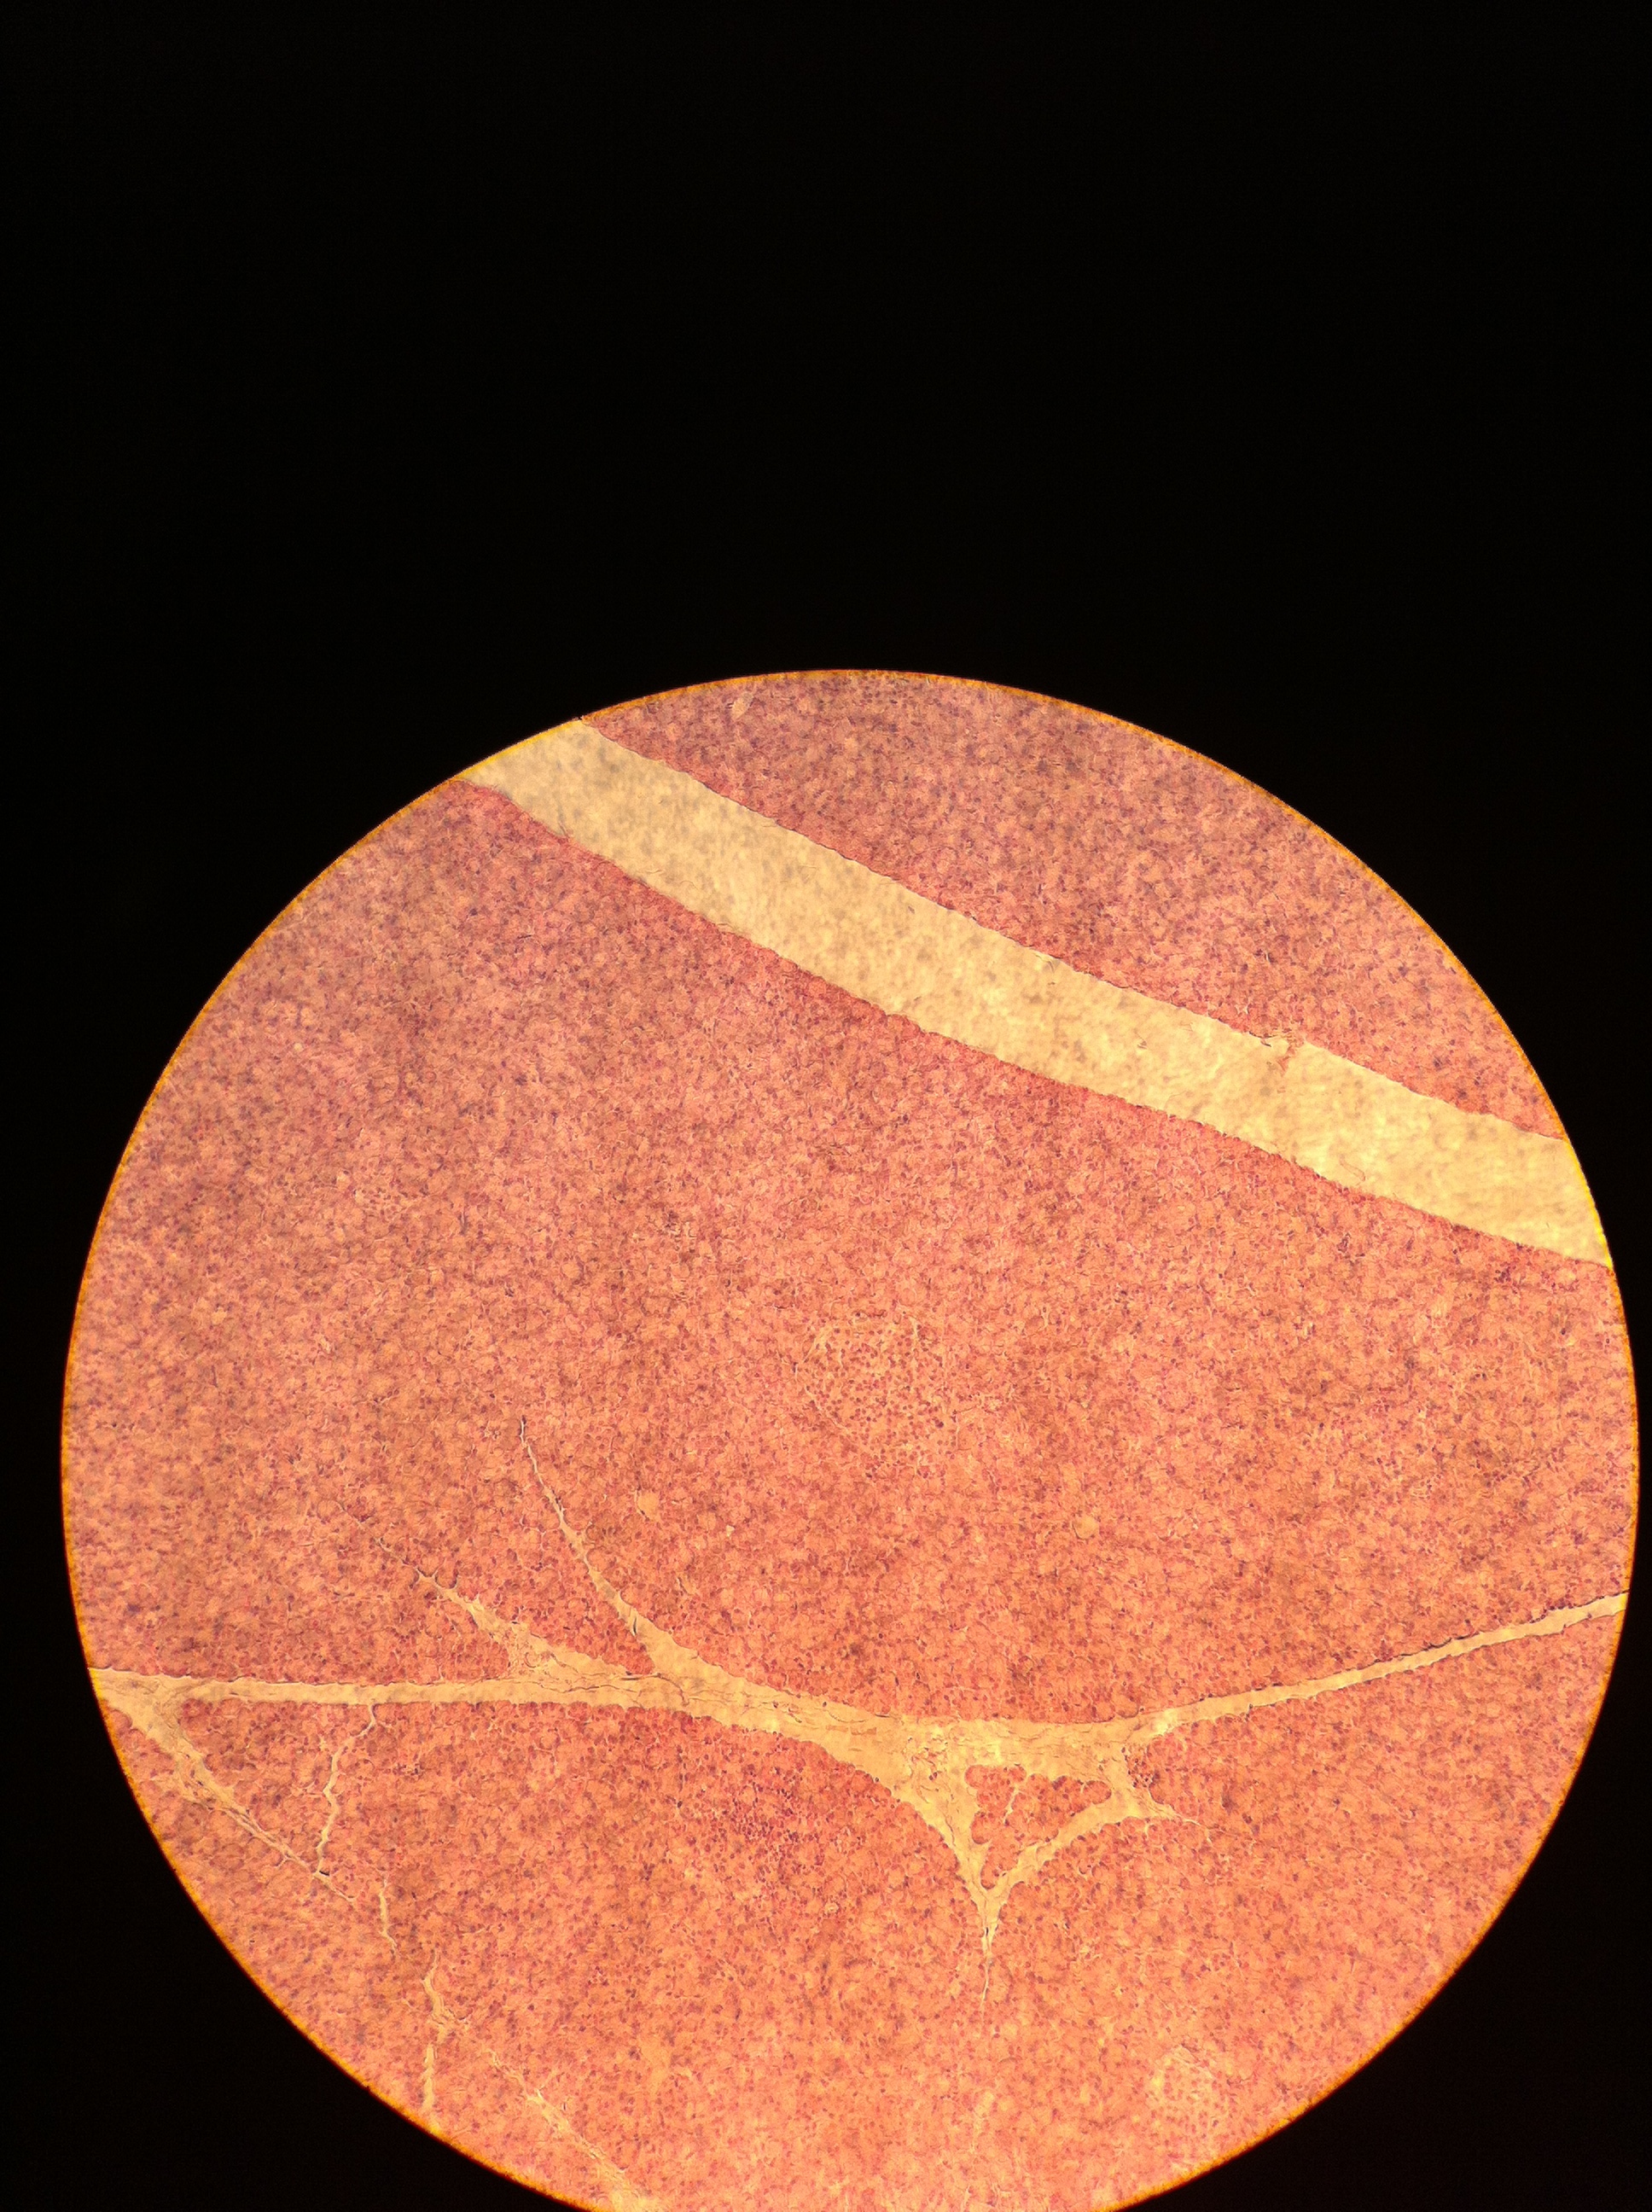

Pancreatic Islet 100X

Pancreatic Islet 400X